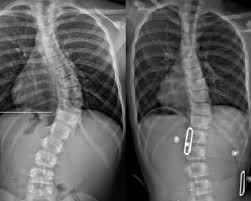

يعاني كثير من الأهل من صدمة أولى عند معرفة سعر حزام اعوجاج العمود الفقري الموصى به لطفلهم. فبعد التشخيص، يظهر سؤال مهم ومشروع: لماذا هذا السعر مرتفع؟ وهل يستحق الحزام هذه التكلفة فعلًا؟

تحليل الأشعة وقياس زاوية الاعوجاج بدقة.